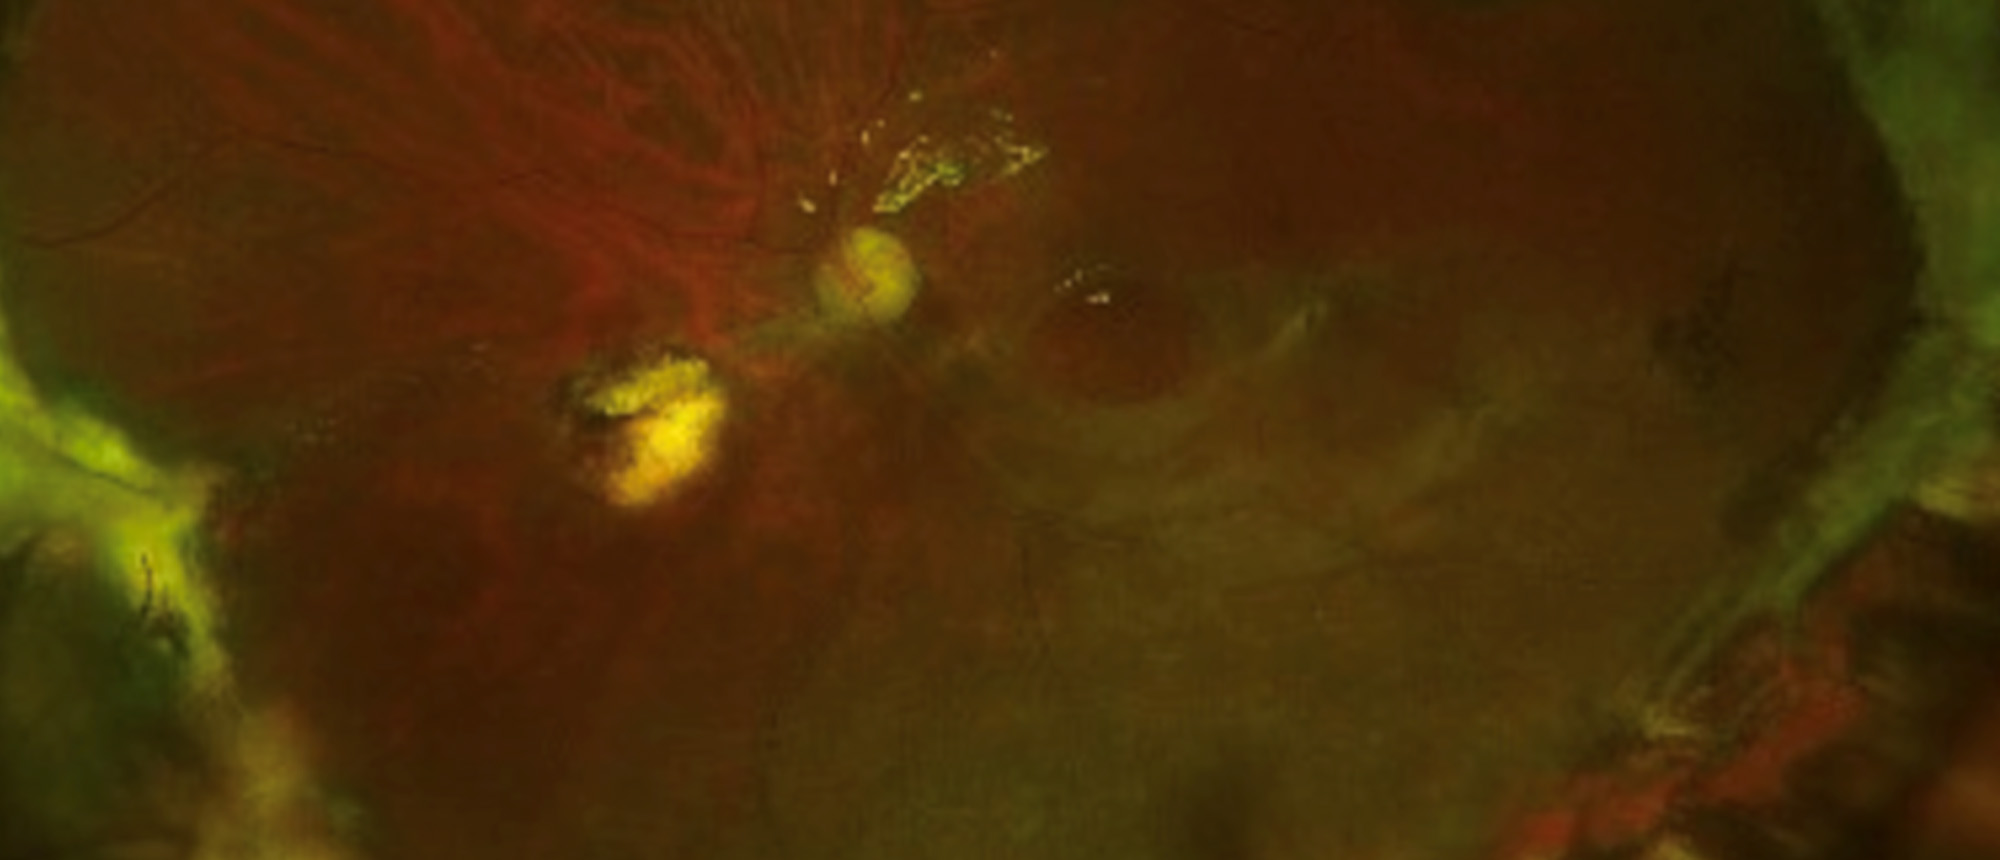

Abstract A middle-aged patient with past medical history significant for HIV (well-controlled on bictegravir, emtricitabine, and tenofovir) and history of Monkeypox infection presents to the emergency room complaining of foreign body sensation, redness, and itchiness in his right eye for two days. …

Intraocular Helminth A middle-aged patient with past medical history significant for HIV (well-controlled on bictegravir, emtricitabine, and tenofovir) and history of Monkeypox infection presents to the emergency room complaining of foreign body sensation, redness, and itchiness in his right eye fo…